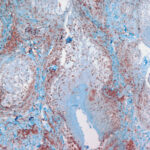

The mucin found in these six diseases represents an increase in the mucin that is normally present in the ground substance of the dermis. It consists of proteins bound to hyaluronic acid (hyaluronan), which is an acid mucopolysaccharide or glycosaminoglycan. As a result of the great water-binding capacity of hyaluronic acid, dermal mucin contains a considerable amount of water. This water is largely removed during the process of dehydration of the specimen; consequently, in routine sections, the mucin, because of its marked shrinkage, appears largely as threads and granules. |

The mucin present in the six types of mucinosis stains a light blue in sections stained with H&E. It also stains with colloidal iron. It is Alcian blue-positive at pH 2.5 but negative at pH 0.5 and shows metachromasia with toluidine blue at pH 7.0 and 4.0 but no metachromasia below pH 2.0 . It is PAS negative (indicating the absence of neutral mucopolysaccharides) and aldehyde fuchsin negative (indicating the absence of sulfated acid mucopolysaccharides). The mucin is completely removed on incubation of histologic sections with testicular hyaluronidase for 1 hour at 37″C . |